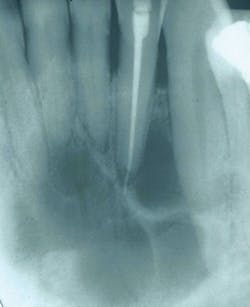

Usually discovered through a radiograph depicting a radiolucent lesion of the mandible or maxilla, the CGCG accounts for fewer than 7% of all benign tumors of the jaws-with a prevalence for the mandible at a 65 to 75% rate and affecting females more often than males. The growth is an intraosseous lesion consisting of cellular fibrous tissue (fibroblasts) that contains multinucleated giant cells. The CGCG is very slow growing. But, when seen in a more aggressive form, it exhibits rapid growth, swelling, loosening of the teeth, displacement of the teeth, and it penetrates the cortical bone (see Figure 1).

Figure 1

Radiographic characteristics: The CGCG is seen as a multilocular lesion or, in rare cases, a unilocular lesion that has well-defined margins. The borders may have a scalloped appearance. The more aggressive form may depict not only root resorption but also perforation of cortical bone.

Perioral and intraoral characteristics: The CGCG are usually painless unless the size and expansion of the lesion becomes excessive. Found primarily anterior to the first molar, radiographic appearances may be noted because of the divergence and expanding margins of a radiolucent lesion. Loss of the lamina dura may be an early indication. Pain along with a noted clinical appearance is usually seen when the lesion penetrates and protrudes through the cortical bone, but not reported initially. The CGCG then may be noted as a soft tissue, flat-based nodule with a blue-to-purple color when this stage of development is obtained.